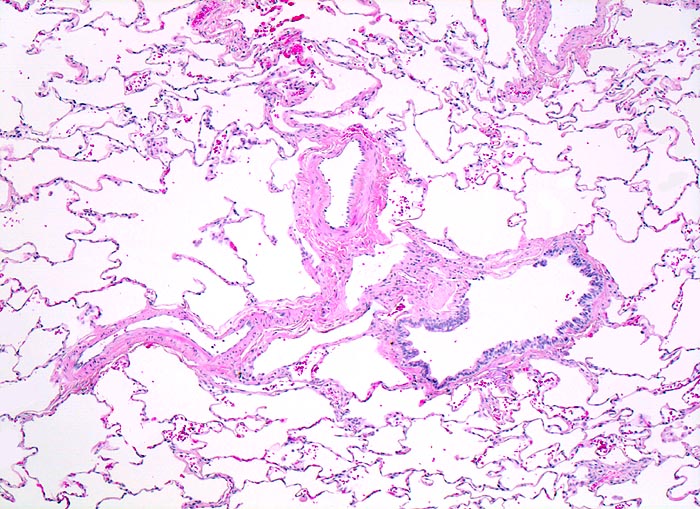

Morphologisch lassen sich zentroazinäre (> 3484), panazinäre (> 3599) und paraseptale Emphyseme (> 3487) unterscheiden sowie das Narbenemphysem in der Umgebung vernarbter Lungenareale. Das zentroazinäre (=zentrolobuläre) Emphysem (vorliegendes Präparat) beginnt primär in den respiratorischen Bronchiolen und breitet sich von dort nach peripher aus. Es spart die terminalen Bronchiolen aus. Diese Form des Emphysems ist assoziiert mit langdauerndem Zigarettenrauchen und befällt bevorzugt die Lungenoberlappen.

Histologisch sind die Lufträume erweitert und enthalten frei flottierende Alveolarsepten mit knotenförmigen Spitzen. Peribronchiolär finden sich beim zentroazinären Emphysem reichlich Ablagerungen von schwarzem Anthrakosepigment.

• Schwarz pigmentierte erweiterte Azinuszentren.

• Fragmentierte Alveolarsepten im Bereich der erweiterten Azinuszentren.

• Bruchstücke von Alveolarsepten und Gefässen im Zentrum der emphysematischen Räume. Das sollte der Kliniker dem Pathologen mitteilen: